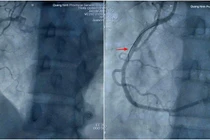

Cứu sống bệnh nhân nhồi máu cơ tim sau mổ nội soi tại Quảng Ninh

Các bác sĩ Bệnh viện Đa khoa tỉnh Quảng Ninh đã kịp thời can thiệp đặt stent, cứu sống bệnh nhân nhồi máu cơ tim đột ngột sau phẫu thuật nội soi.

Mới đây, các bác sĩ Bệnh viện Đa khoa tỉnh Quảng Ninh đã "cân não" can thiệp đặt stent mạch vành giành lại sự sống cho một bệnh nhân bị nhồi máu cơ tim cấp xuất hiện đột ngột sau ca phẫu thuật nội soi, một tình huống tiềm ẩn nhiều nguy cơ biến chứng nặng.

Bệnh nhân Nguyễn Văn Q. (52 tuổi, trú tại phường Móng Cái 1, tỉnh Quảng Ninh), nhập viện với chẩn đoán sỏi túi mật, được chỉ định mổ nội soi cắt túi mật. Trước mổ, bệnh nhân đã được khám tổng quát các chuyên khoa, kiểm tra huyết áp, điện tim cùng các chỉ số xét nghiệm đều trong giới hạn bình thường, đảm bảo đủ điều kiện phẫu thuật. Ca mổ diễn ra thuận lợi, người bệnh tỉnh táo, sinh hiệu ổn định.